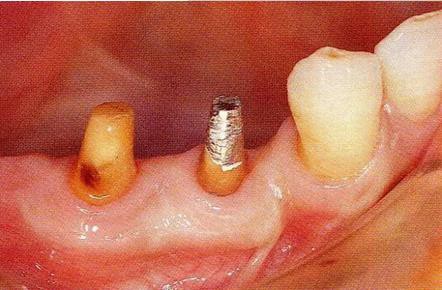

病例4  維系鄰牙的骨水平的戰(zhàn)略性拔牙:

圖17-1 ( 左 ),2  ( 右 ) ▲  右下4近中9mm的骨緣下缺損,兩側(cè)全口橋體修復(fù),但是這顆患牙保留的情況下會(huì)影響牙列的維持,鄰接牙的骨水平在較高的位置,拔牙后可以獲得平坦的骨水平。即使是右下4嘗試再生療法,假說(shuō)可以100%的成功,右下3遠(yuǎn)中骨水平也會(huì)形成3mm以上的臺(tái)階。而且再生治療也需要患者登上1年半以上的時(shí)間。所以最終選擇拔牙的處理。